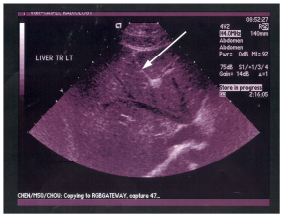

61 附圖為右上腹部縱向超音波掃描,箭號所指的構造為: (A)肝外膽管(extrahepatic bile duct) (B)肝內膽管(intrahepatic bile duct)(C)肝靜脈 (D)門靜脈

62 附圖中箭號所指的解剖結構為: